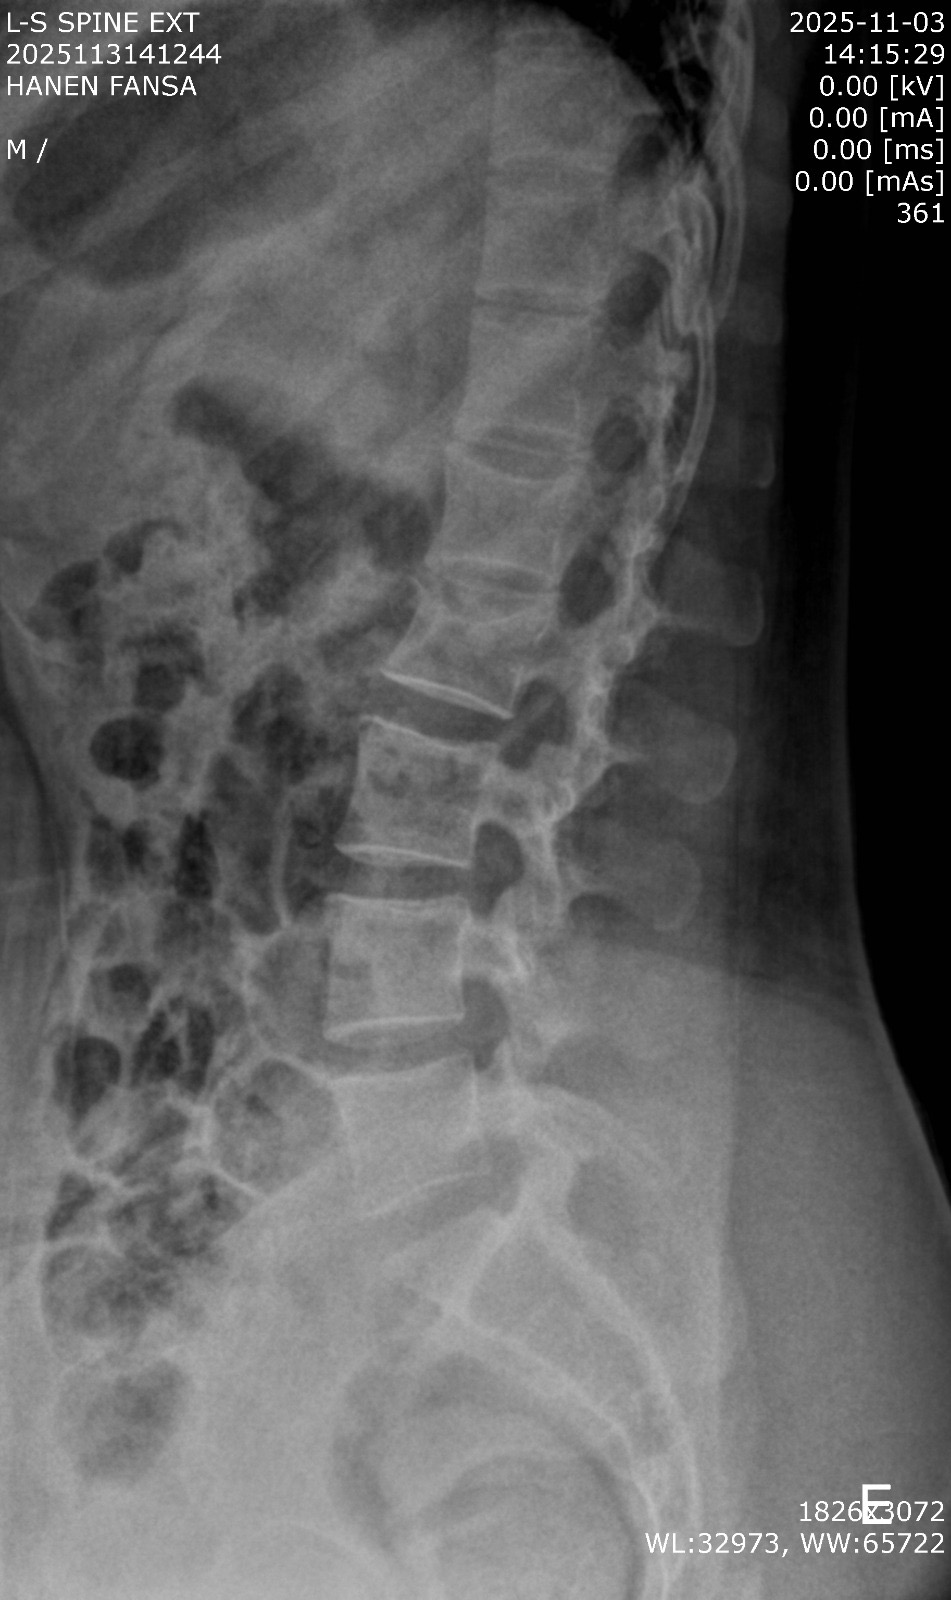

ما هو تقييم الأطباء ونتائج الصور الشعاعية الجديدة التي أجريتها بعد شهر من الالتزام بالراحة والاستلقاء واستخدام المشد الحديدي لعلاج كسر الفقرة القطنية الثانية (L2)، وهل تشير هذه النتائج إلى وجود تحسن في حالة الكسر والتعافي؟

جيد مافيش رجوع للجدار الخلفي ولا تضييق على قناة النخاع و اعراض التجبر بدات تظهر لكن يجب الالتزام بالراحة ومواصلة ارتداء الدعامة 0 2025-11-05T03:51:44+00:00

جيد مافيش رجوع للجدار الخلفي ولا تضييق على قناة النخاع و اعراض التجبر بدات تظهر لكن يجب الالتزام بالراحة ومواصلة ارتداء الدعامة